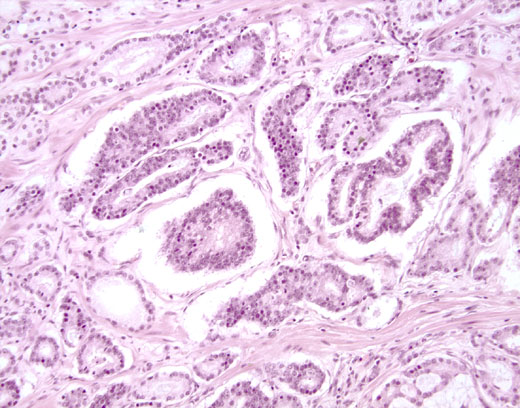

Cross-section #59 - 20X

click on the slide photo to see 40X magnification